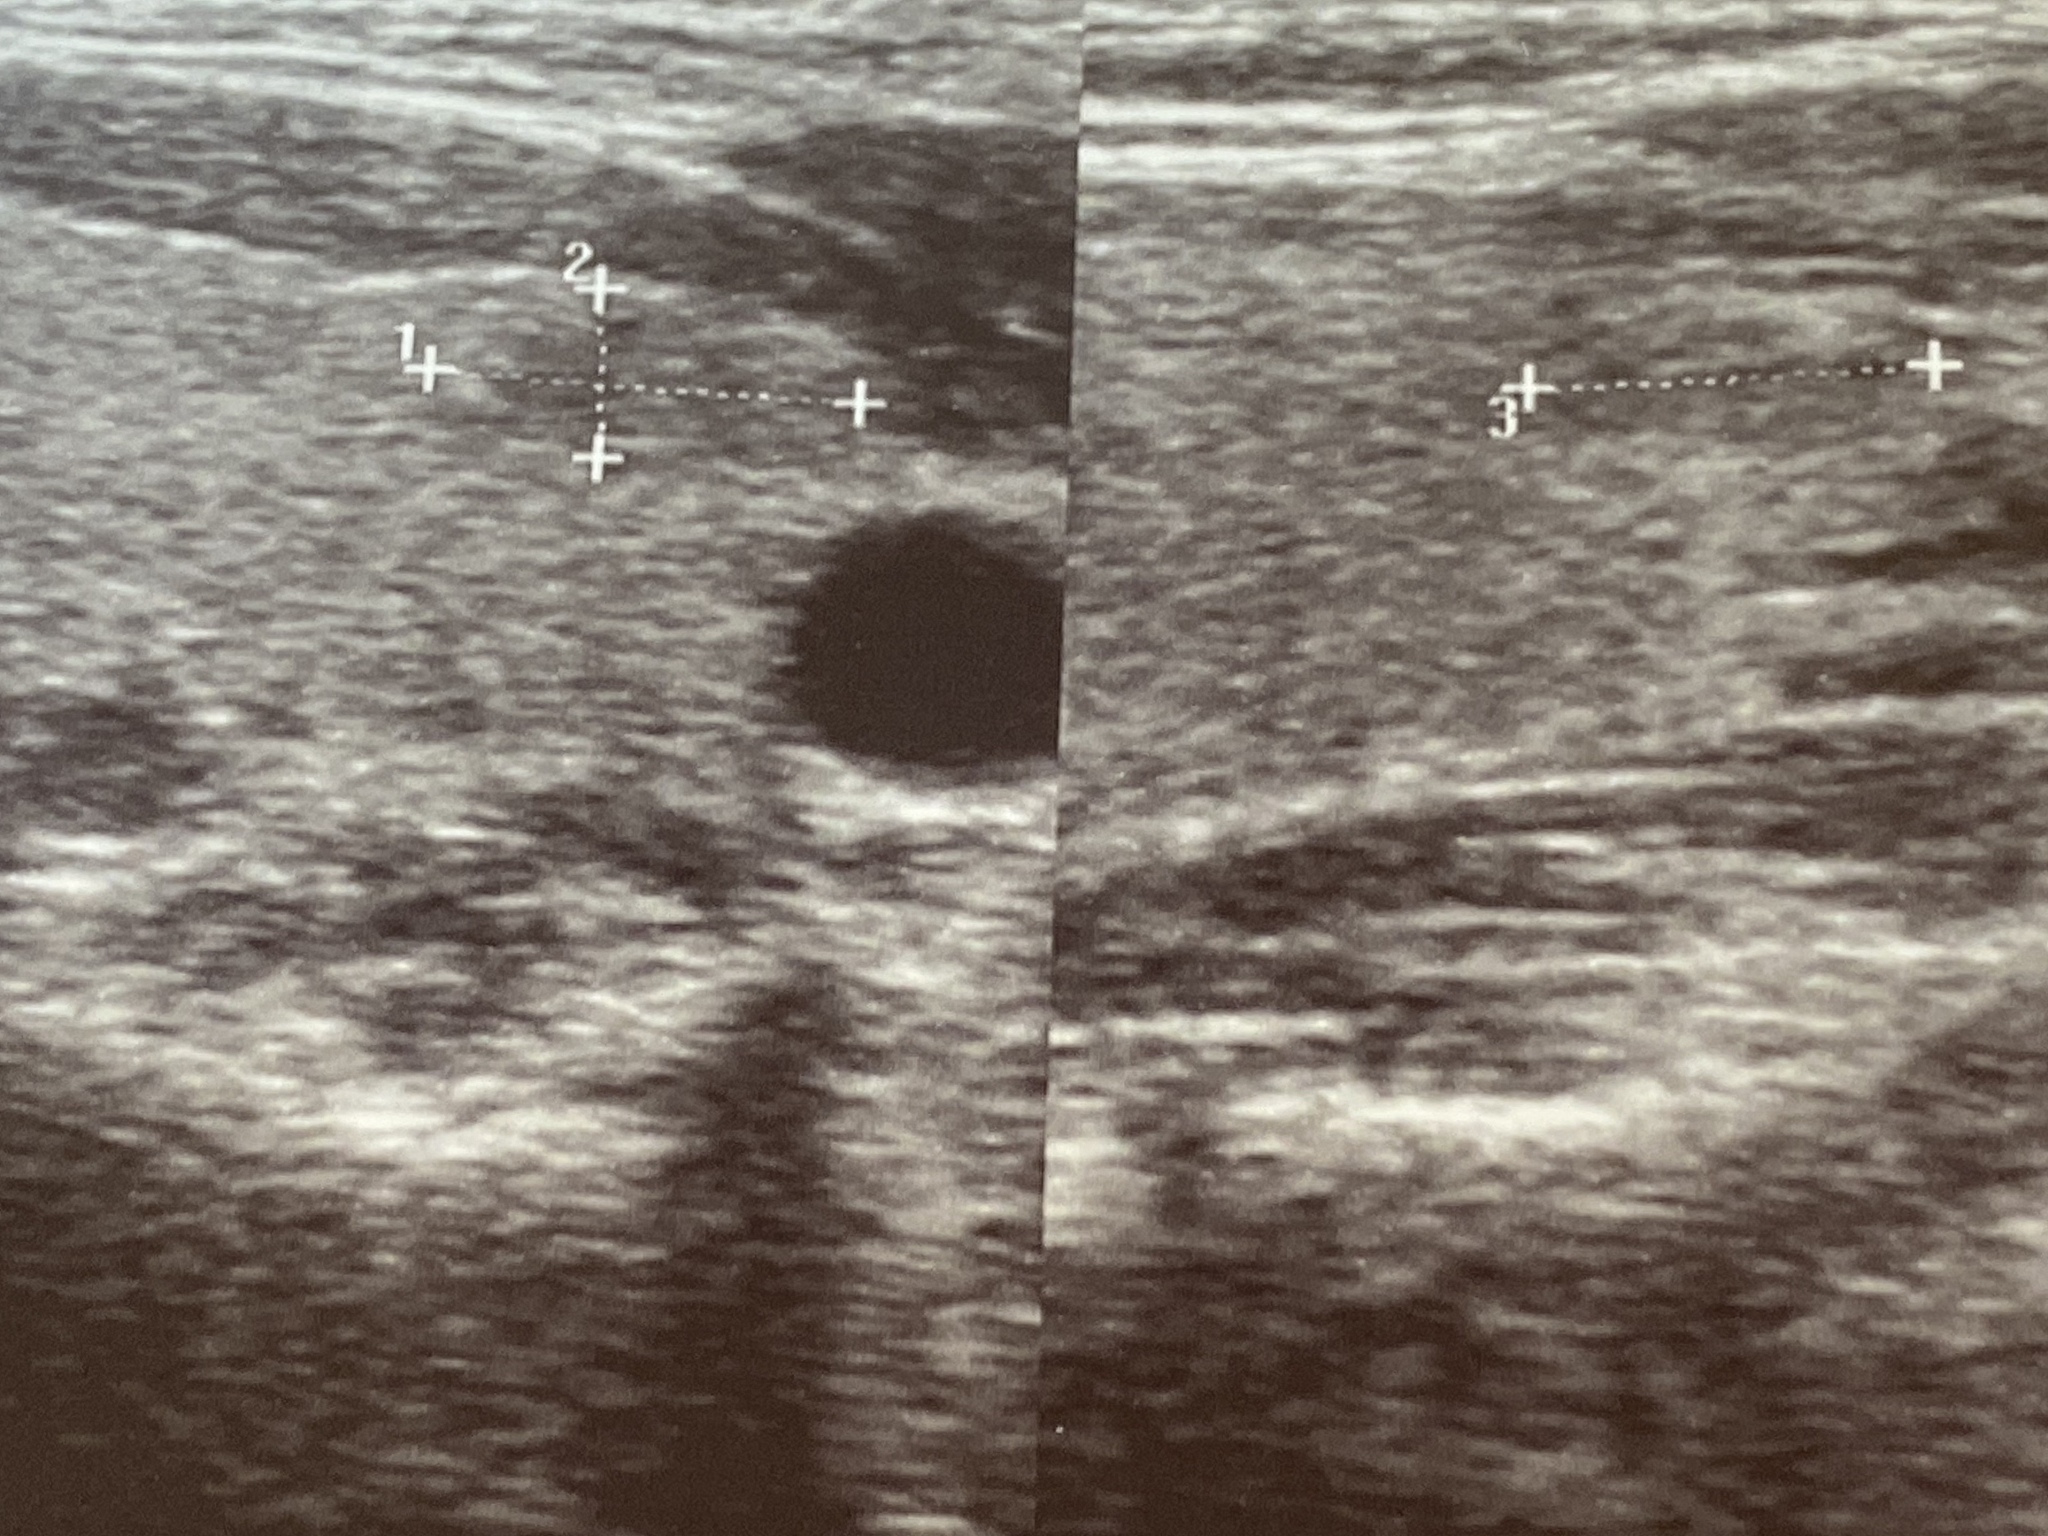

2. 超声检查:超声波可以生成甲状腺的图像,帮助医生确定肿瘤的位置、大小和形态。

4. 活检:如果超声检查发现可疑的肿块,医生可能会建议进行甲状腺活检。活检是通过穿刺甲状腺肿瘤,取得组织样本进行病理学检查,以确定是否为恶性肿瘤。